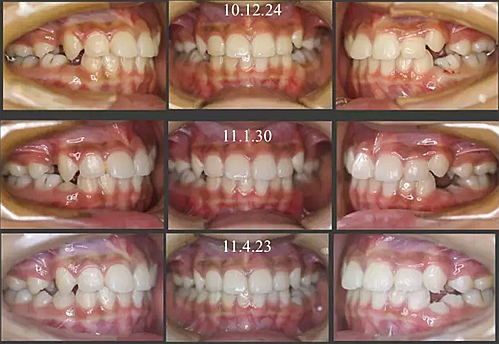

經(jīng)過我臨床檢查和X線的診斷,決定早期干預(yù),每三個月定期復(fù)診檢查一次,并拔掉了幾個乳牙和四個恒牙,正畸專業(yè)叫序列拔牙。

5.png

經(jīng)過三年零九個月的看護,最終戴上了固定矯治器,但是大家不難發(fā)現(xiàn),孩子的牙齒已經(jīng)排齊,上下中線也基本對齊,面型也好看多了,這樣矯正就變得簡單,療程自然縮短,孩子也不遭罪了。

這個故事告訴我們,只有家長早點把孩子帶給正畸醫(yī)生檢查,才能早期發(fā)現(xiàn)早期治療。起到了事半功倍的效果。矯正以后還不容易復(fù)發(fā),因為從08年的初診到11年戴矯正器這三年多的時間里,孩子的牙齒是自己長好的。